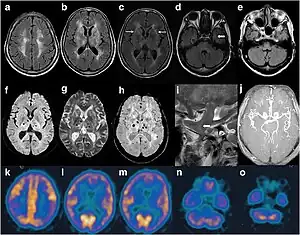

Cranial imaging of an FFI patient. In the MRI, there are abnormal signals in the bilateral frontoparietal subcortical area. MRA showed smaller distal branches of cerebral arteries.